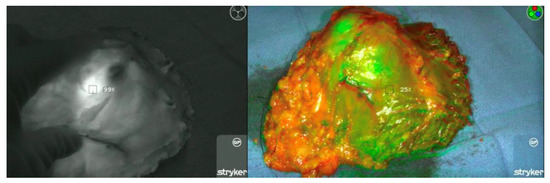

Intraoperative Evaluation of Soft Tissue Sarcoma Surgical Margins with Indocyanine Green Fluorescence Imaging

3.2. ICG Dosage, Duration, and Detection

3.3. ICG Margin Comparison